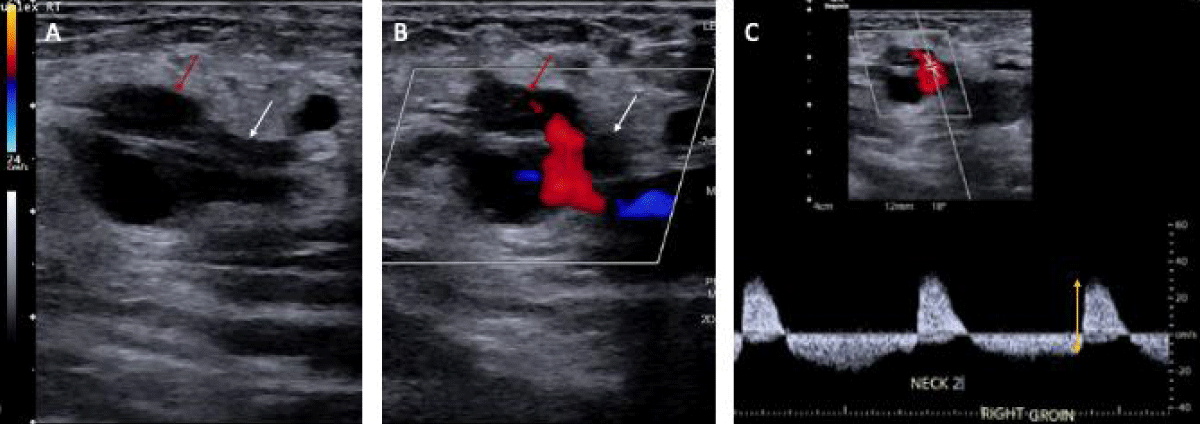

A 65-year-old woman with a history of coronary artery bypass grafting for severe coronary artery disease, mechanical mitral valve replacement on warfarin, persistent atrial fibrillation, and heart failure with reduced ejection fraction, presented with a two-day history of increased urination, fever, and bilateral flank pain. She was admitted for urosepsis and treated with intravenous fluids, vancomycin, and cefepime. Vancomycin was discontinued after blood cultures grew no bacteria at 48 hours and cefepime was continued for a total 5-day course. On day two of admission, her high sensitivity troponin increased from 24 ng/L to 1509 ng/L with EKG changes significant for atrial fibrillation with rapid ventricular response with a previously known left bundle branch block. There were no ST elevations or T wave inversions. Given her history of coronary artery disease and high suspicion of acute coronary syndrome, warfarin was transitioned to heparin, and she underwent cardiac catheterization via a right femoral access under ultrasound guidance. The Heparin drip was discontinued immediately before patient transportation for the catheterization. Right radial access was initially attempted but was unsuccessful due to radial artery vasospasm. Angiography showed no obstructive Coronary Artery Disease (CAD) and normal right heart pressure. Post-catheterization, the femoral access site was dressed with gauze and Tegaderm. Given the lack of CAD, troponin elevation was attributed to demand ischemia in the setting of sepsis. Four days post-catheterization, she developed new right lower quadrant pain and hypotension. Later the same day, the on-call team was notified that the hematoma in the right lower quadrant noted on ultrasound was rapidly expanding. Upon confirmation, the heparin was immediately discontinued, and the patient was upgraded to the medical intensive care unit. Initial computed tomography of the abdomen and pelvis (CTAP) was significant for a large right rectus sheath hematoma measuring 17 x 10 x 17 cm with concern for active extravasation from the right inferior epigastric artery. Subsequently, a right iliofemoral angiogram was performed for further characterization of the bleeding source and demonstrated a right Common Femoral Artery (CFA) hemorrhage into a PSA, not an inferior epigastric artery hemorrhage (Figure 1). The patient received Ultrasound-Guided Thrombin Injection (UGTI) with 300 units of thrombin injected into the right CFA PSA sac and closer to the neck with successful thrombosis and no further color flow within the PSA on repeat imaging. Heparin was re-started on day three, post-hematoma onset, after an in-depth risk-benefit discussion with the family. Bridge to warfarin was started on day ten post-hematoma onset after ensuring hematoma stabilization, hemoglobin stability, and no signs of skin ischemia or necrosis. 19 days after initial hematoma onset, a CTAP demonstrated the rectus sheath hematoma measuring 11.4 x 18.5 x 22.2 cm (Figure 2). The patient was discharged to an acute inpatient rehab facility and was later discharged from rehab after 14 days. Two months after the initial hematoma onset, an outpatient monitoring ultrasound was performed and showed a well-circumscribed heterogeneously hypoechoic structure measuring 15.5 x 14.0 x 10.5 cm. The patient had no further occurrences of bleeding

Download Image

Figure 1: Two-dimensional ultrasound representation of the femoral artery pseudoaneurysm in our 65-year-old patient. A) PSA sac (red arrow) and neck (white arrow) without color flow. B) PSA sac and neck with color flow showing inflow at the neck. C) Waveform showing bidirectional flow in the PSA (yellow double-sided arrow).

Arterial duplex ultrasound is the first-line imaging modality for assessing arterial blood flow within the PSA using color Doppler [4]. Color flow within the pseudocapsule demonstrates a bidirectional blood flow pattern known as a ‘yin-yang sign’ characteristic of PSAs and larger aneurysms. Iatrogenic PSA typically develops within 24 hours post-procedure; however, it may still occur up to 7 to 10 days after the inciting event. Regardless, they should be treated emergently, especially when presenting with hemodynamic instability and a rapidly evolving hematoma, as was described in this patient.